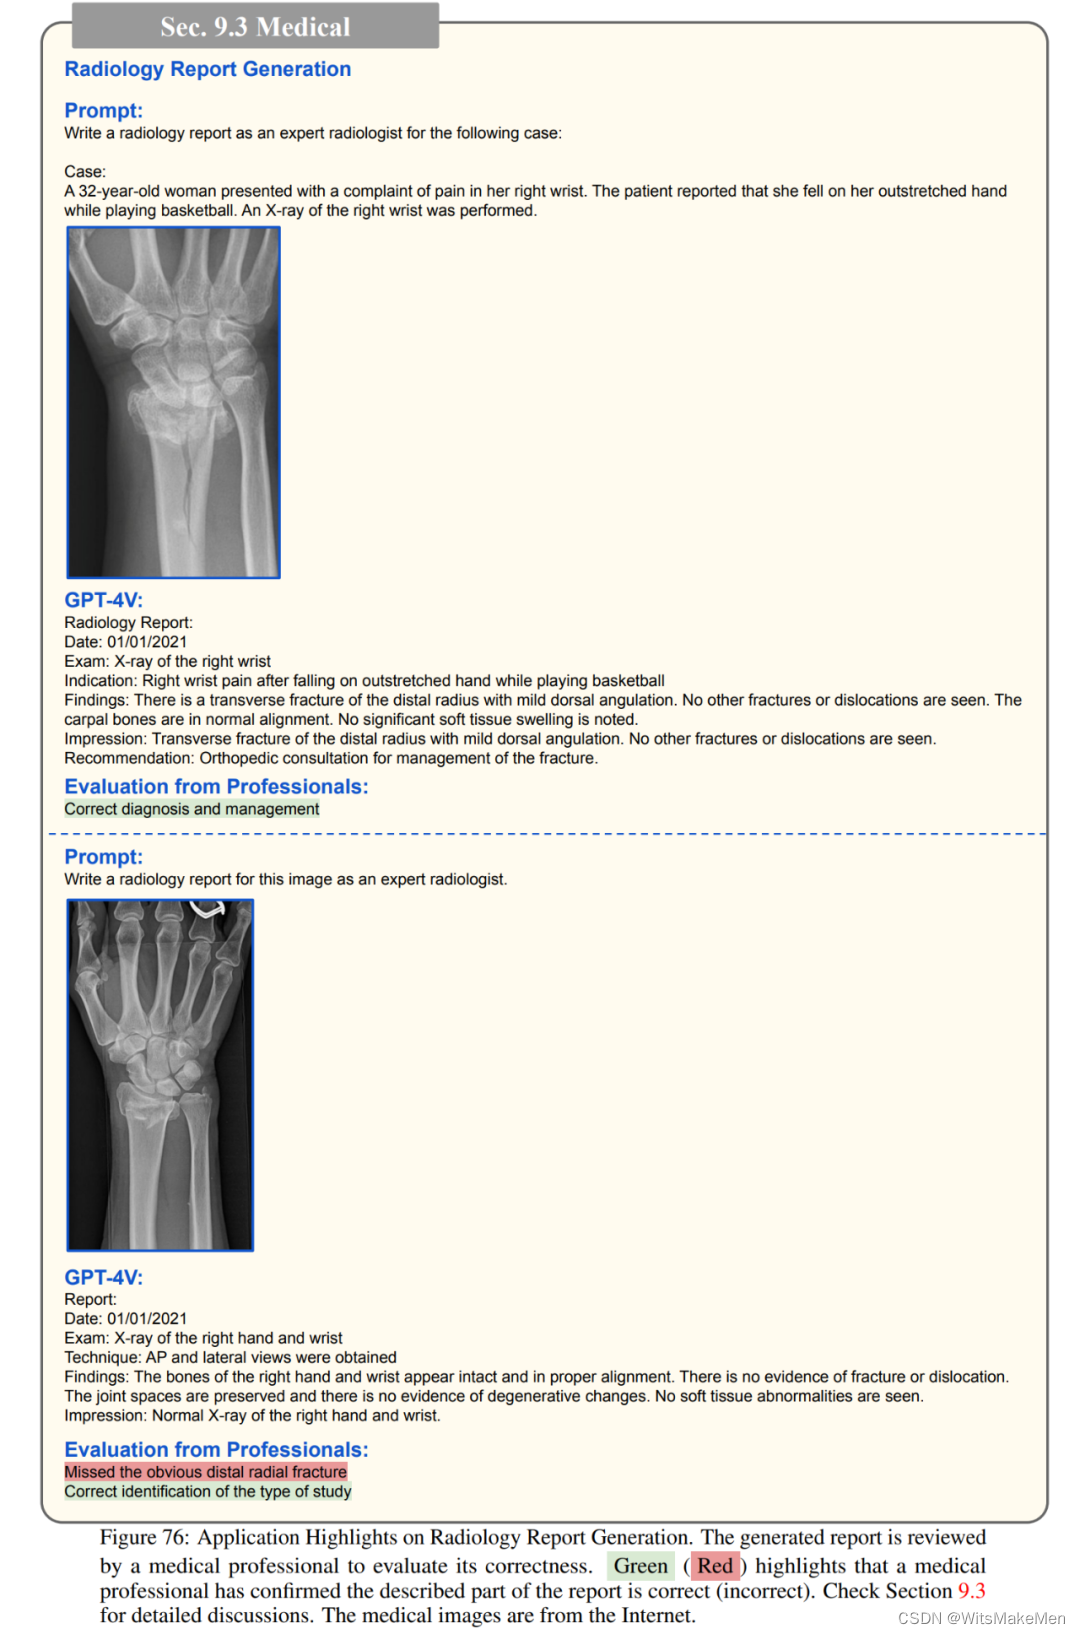

医药